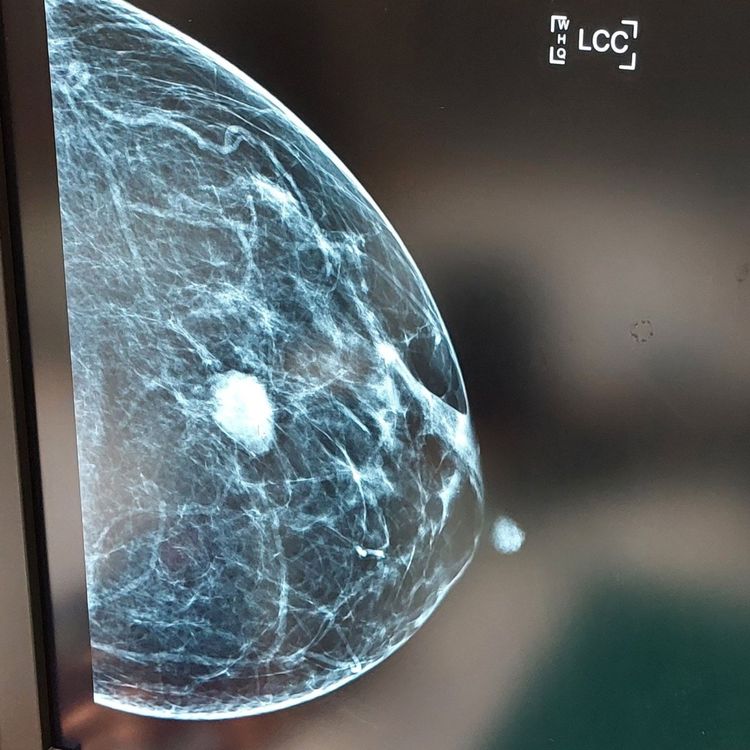

而輔大醫院家醫科醫師李思潔醫師則提醒,政府也有推動婦女乳房X光攝影檢查,針對「45-69歲婦女」和「40-44歲且二親等以內血親曾患乳癌之婦女」提供每2年1次的免費乳房攝影。

至於年輕女性是否應該也要自費定期做乳房攝影,醫師表示,因為年輕女性的乳房組織較為乳房比較緻密,緻密型乳房透過乳房攝影,偵測的敏感度較低,因此若有需要,通常要搭配乳房超音波來彌補不足。若可以,也建議成年女性一年進行一次乳房超音波檢查,定期追蹤健康狀況。